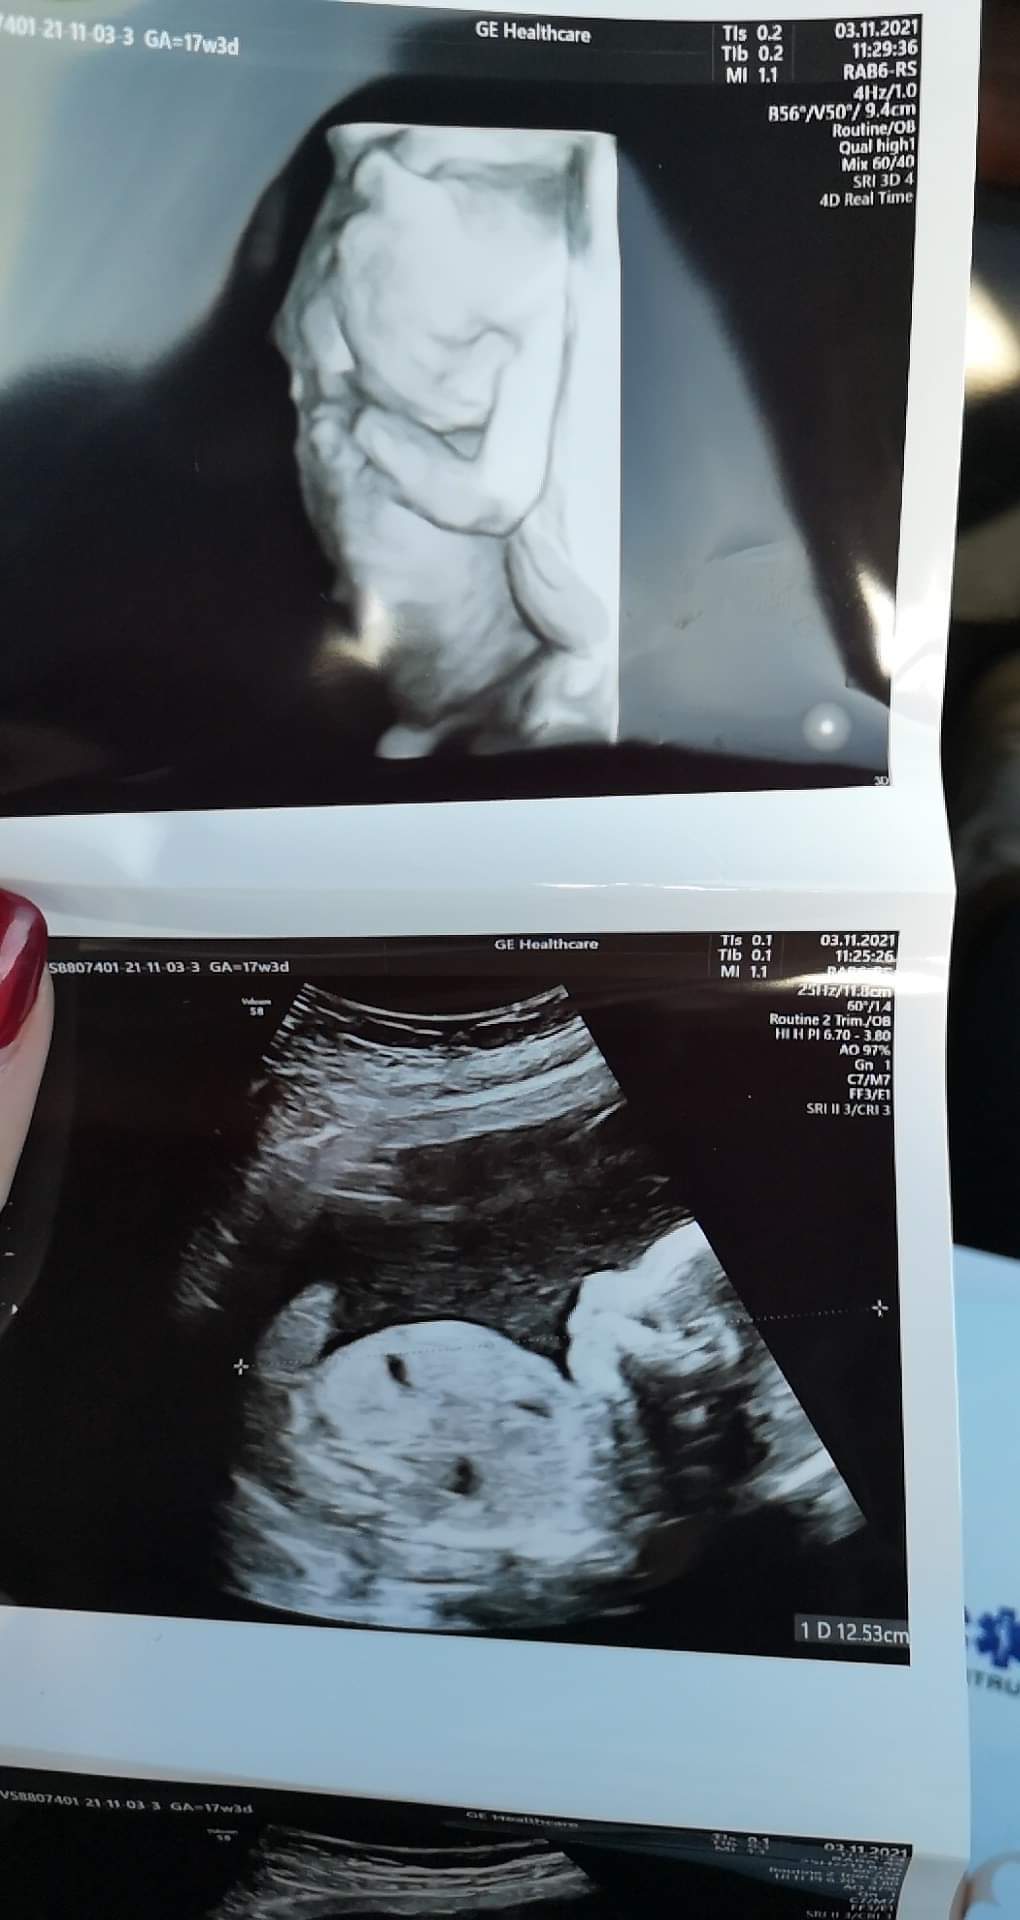

A więc na wizycie super bo zobaczyłam naszego synusia i tatuś też, wszystko jest okej i 2 grudnia mamy połówkowe 😊 niestety doszła mi anemia.. Aż nie mogłam uwierzyć, że ja.. Nigdy nie miałam problemu z żelazem bo zawsze było bardzo ładne bo zawsze w okolicy 120 😁 a teraz mówią, że mam anemię bo hemoglobina niska... 😐 Dostałam rozpiske jak jeść i zobaczymy za miesiąc jaki będzie wynik 🙄 dzidziuś wyciąga ze mnie wszystkie witaminki 🙈 odrazu były pytania czy nie chodzę jakaś zmęczona i czy męczę się szybciej.. Myślam, że to poprostu objawy ciąży 😁 ważne, że z dzidziusie wszystko okej ❤️ przepraszam jeśli tak bez ładu i składu ale 😅 dzidziuś wyprostowany ma 20 cm, i był dzisiaj bardzo ruchliwy i pani doktor miała gimnastykę, serio musiałbyście widzieć to uzg 😂

A tu zdj ❤️